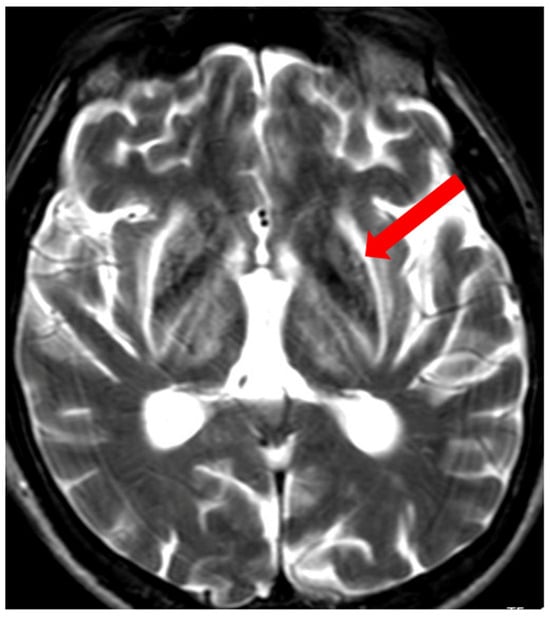

3.1. Classical Brain MRI Examination in WD Patients

5. Neuroradiological Pathognomonic Signs of WD